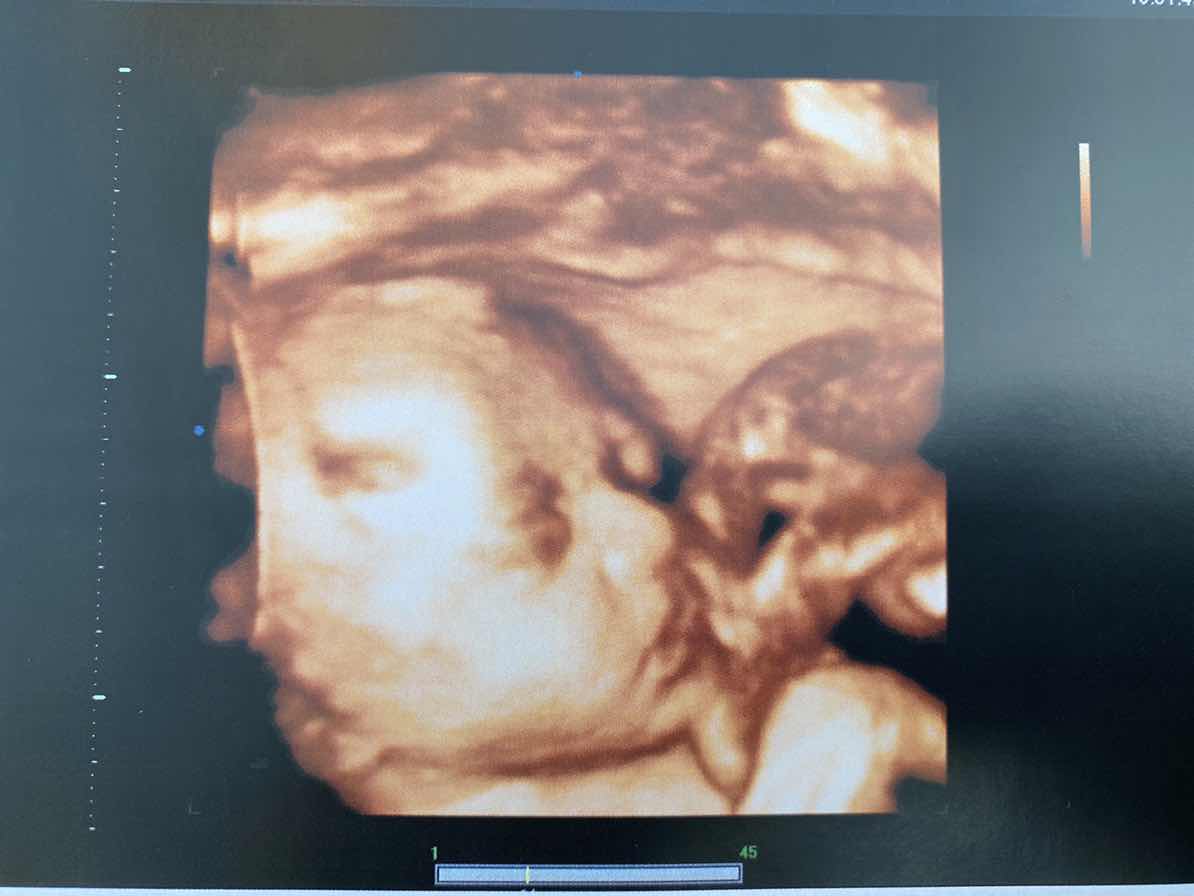

เห็นหน้าชัดกันมั๊ยคะ บ้านนี้ เอามือบังตลอดเลยค่า หมอเขย่าท้องก็แล้วไม่เอาออกเลยย ??

บ้านนี้ก็บังจ้าาาา